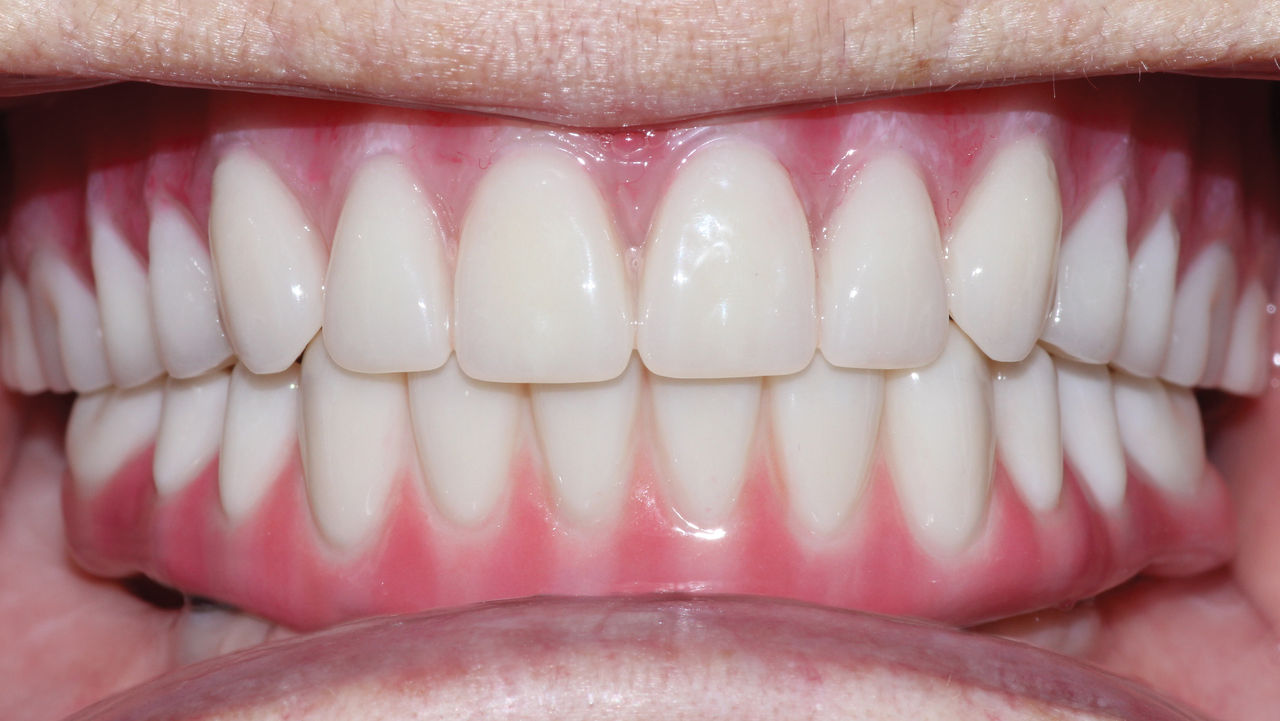

The patient’s remaining mandibular teeth were extracted followed by immediate implant placement and delivery of a fixed provisional appliance. After integration of the implants, the prosthetic designs for the new upper denture and lower implant restoration were determined in tandem. Ultimately, the dual-arch restorations addressed the functional and esthetic challenges of the case while staying within the financial means of the patient, demonstrating the benefits of a flexible, multifaceted approach to restorative dentistry.

The dual-arch restorations addressed the functional and esthetic challenges of the case while staying within the financial means of the patient.

When providing treatment for the edentulous arch, the ability to offer traditional removable dentures as well as implant-supported prostheses affords the flexibility required to address the various needs of patients. By carefully considering the oral health, anatomy and financial circumstances of each case, clinicians can devise a treatment plan that effectively restores form and function within the budget of the patient.